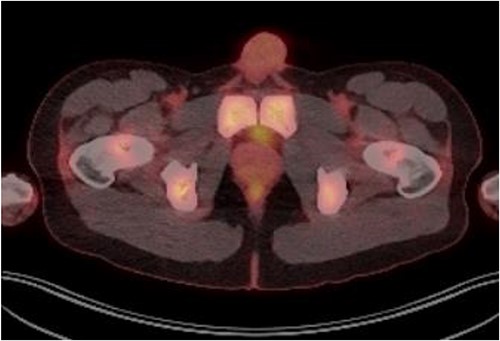

Laboratory tests of full blood count and liver function test were unremarkable with prostate specific antigen of 0.53. Mid-stream urine MCS did not show any infection and urine cytology was negative. Renal function test revealed progressive worsening of previously normal eGFR down to 27 ml/min. Initial renal tract ultrasound (Fig. 1) showed enlarged prostate indenting into the bladder base with high post micturition urine residual volume of 185 ml but no hydronephrosis. CT KUB (Fig. 2) showed irregularly enlarged prostate with bilateral hydroureteronephrosis. MRI prostate showed enlarged prostate with PIRADS 5 amorphous mass suspicious for carcinoma involving bilateral seminal vesicles and right vesicouretric bladder. FDG PET (Fig. 3) showed unusual distribution pattern of lymphoma involving the prostate with bilateral symmetrical renal, early pulmonary, and possibly right thyroid lobe involvement.

PET FDG scan pre-R-CHOP chemotherapy showing disease activity in the prostate.

Patient was catheterised and subsequently underwent bilateral ureteric stenting. Cystoscopic views of the prostate was also abnormal and concerning for malignancy, so transperinal prostate biopsy was performed. Histology of this confirmed diffuse large B cell lymphoma. Renal function improved post ureteric stenting and patient was referred to haematology for management of DLBCL. Progress FDG PET scan (Fig. 4) 3 months post R-CHOP chemotherapy showed complete metabolic response with no avid residual lymphoma.